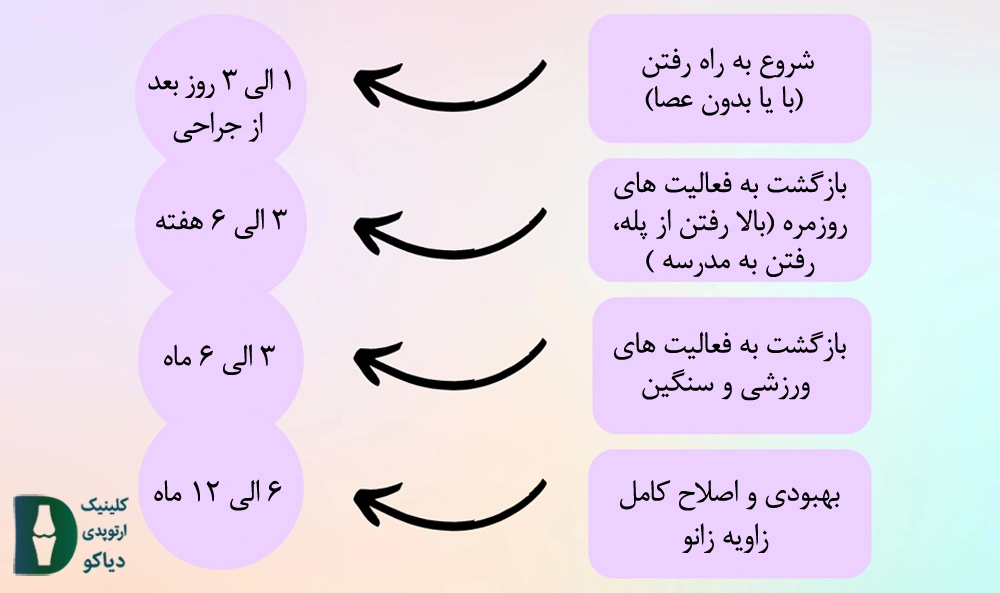

زمان بازگشت به فعالیت را می توانید در شکل زیر مشاهده نمایید:

زمان بازگشت به فعالیت پس از انجام جراحی تعویض مفصل زانو به عواملی نظیر قدرت بازیابی فرد، مهارت پزشک و … بستگی دارد. با این حال در شکل زیر مدت زمان تقریبی بازگشت به فعالیتهای مختلف شرح داده شده است: